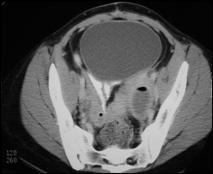

Bilateral tubo-ovarian abscesses with gas

Right                                                             Left